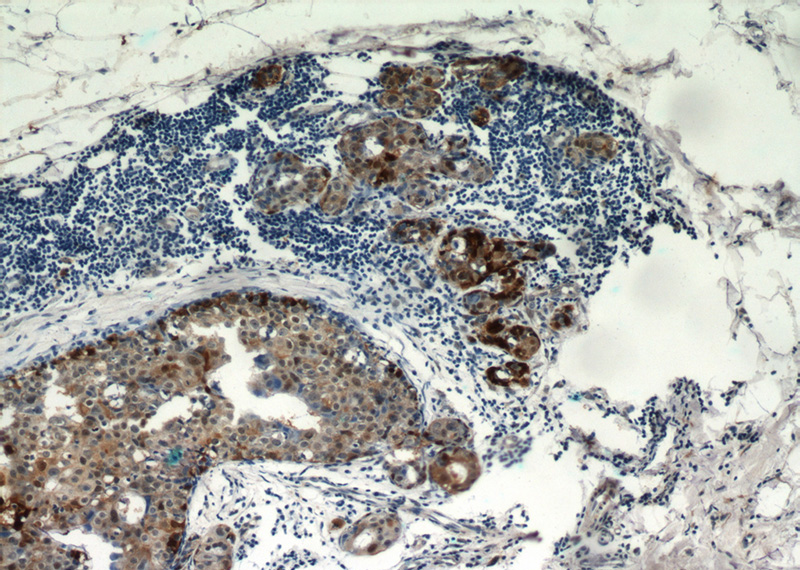

Immunohistochemical of paraffin-embedded human breast cancer using Catalog No:108861(CARM1 antibody) at dilution of 1:50 (under 10x lens)